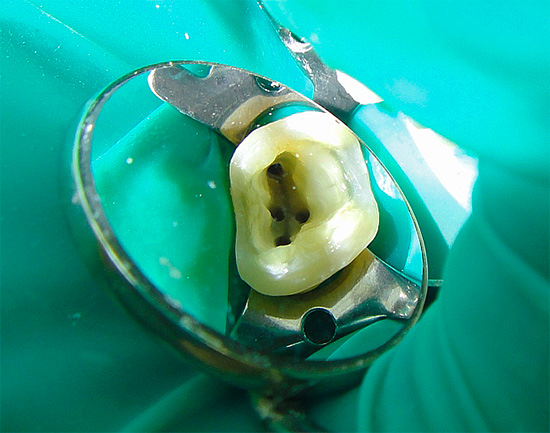

Cosa farà il dottore se il dolore ai denti è dovuto alla pulpite?

Se, ad esempio, a causa della carie profonda, il "nervo" del dente è stato infettato, il medico tratterà tale dente in una o più visite. Innanzitutto, l'anestesia viene eseguita, una camera di polpa viene aperta con un trapano, il "nervo" viene rimosso, i canali all'interno della radice vengono puliti, lavati, sigillati e un riempimento viene posizionato sulla parte superiore del dente.